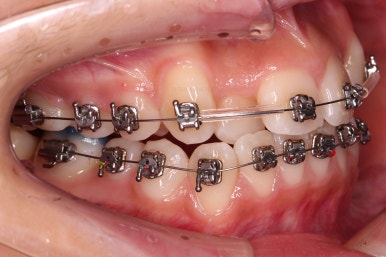

이번 환자분이 선택하신 장치는 엠파워 메탈이라고 하는 자가결찰 금속 장치에요.

메탈 장치라고 모두 구식의 옛날 안좋은 장치라고 생각하시면 안되고, 자가결찰 인지 아닌지 여부가 훨씬 중요하다고 거듭 말씀드렸지요.

자가결찰이기만 하면 치료 효과 동일하며, 단지 성분이 메탈이냐 세라믹이냐에 따라 보이는 정도, 부피, 모양 등이 약간 차이가 있을 뿐이에요.

가지런하게 하면서 안으로 쏙 들어가있는 앞니를 가지런하게 할 자리 확보부터 해줍니다.

자리 확보 이 후에 가지런하게 해주는데요.